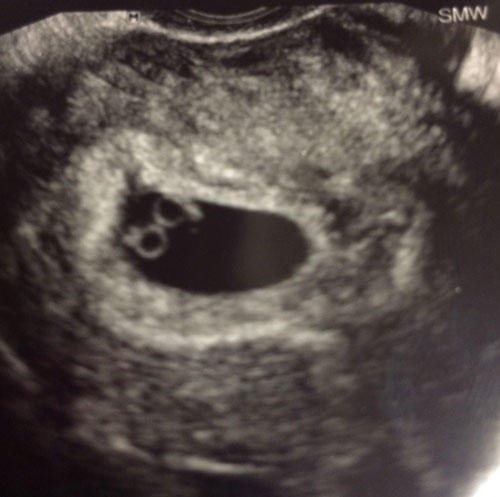

On 4/17/17 exactly 5 months after surgery we found out there is two little hearts beating. The next ultrasound and more information will be in 4 weeks.